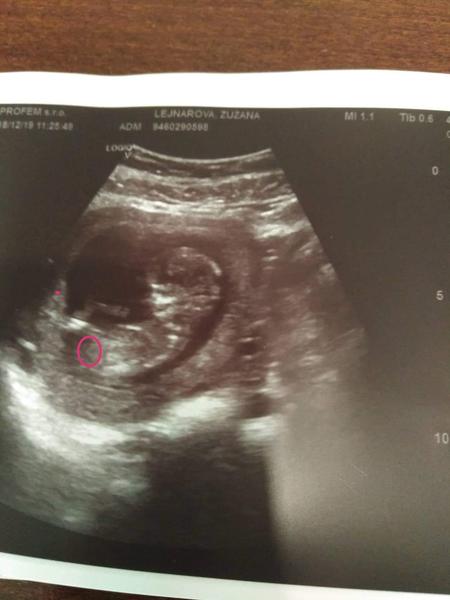

Holky a pradte co vidite u nas? Utz je 15+2. Uz mam oci vykoukany. V krouzku je mozna pohlavi? Nebo si to namlouvam?